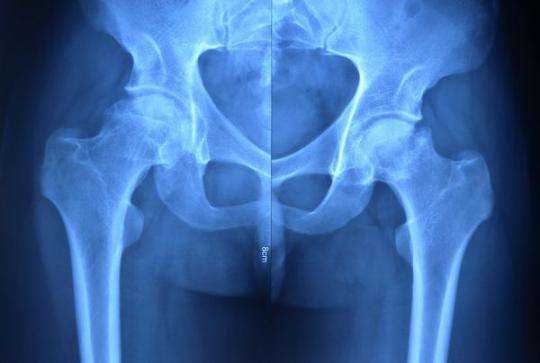

3.影像学:必要的应脊柱或骨盆(包括骶髂关节和髋关节)X线、MRI,对治疗方案决策和调整有重要指导作用;